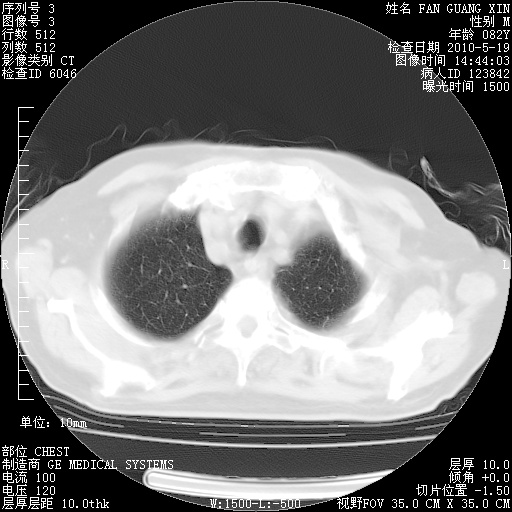

复查肺部CT,明显好转。为什么发热呢?

治疗3周后的肺部CT

治疗3周后的肺部CT纵隔窗